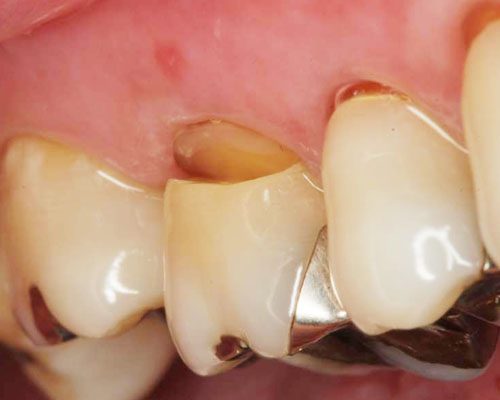

歯の根元が欠ける

大小いろいろありますが、どれも歯ぎしりなどの力によって歯の根元が欠けてしまったものです。見るからに知覚過敏が起きていそうですね。ここまで大きなものは珍しいですが、意外と患者さんは気づいていないことが多いのも興味深いところです。